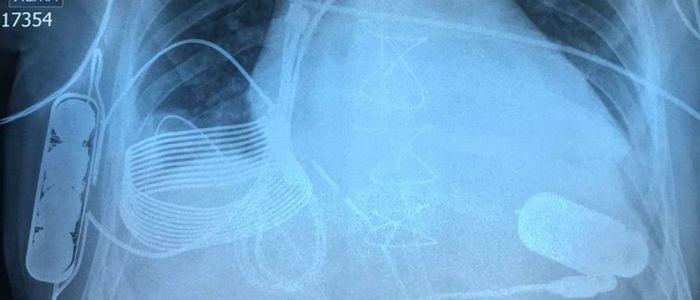

24-річний чоловік страждав від серцевої недостатності в останній стадії, коли в грудні лікарі в Казахстані вживили йому VAD. Але пристрій в грудях Турсунова відрізняється від будь-якого іншого - воно заряджається через бездротову мережу, усуваючи одну з найбільших точок відмови в пристрої, який не може дозволити собі вийти з ладу.

Система складається з індуктивної котушки приймача, акумулятора і внутрішнього контролера, які все імплантовані в груди Турнсунова. Пристрій отримує близько восьми годин роботи від однієї зарядки, і коли Турсунову потрібно його зарядити, він одягає жилет з зовнішньої котушкою, яка заряджає внутрішню котушку електромагнітним способом.